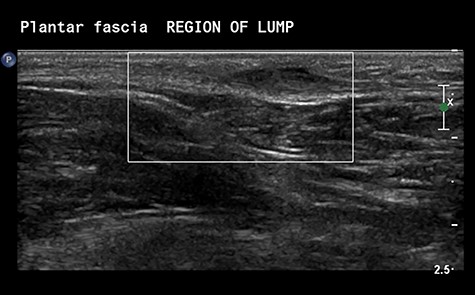

A Caucasian 13-year-old female was referred to our orthopaedic service for assessment of a painful lump on the sole of the left foot, causing pain on ambulation. Clinical examination demonstrated a 20 × 10 mm nodule on the plantar aspect of the foot with tenderness on deep palpation. Ultrasonographic evaluation confirmed the presence of a fibroma attached to the plantar fascia measuring 14 × 4 × 9 mm (Fig. 1).

Ultrasonographic Images demonstrating the presence of a nodule embedded in the plantar fascia.